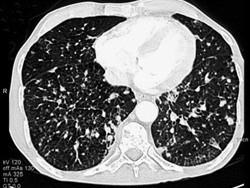

女,56岁,乳腺癌手术后,未行化疗,结合CT图像,选择最可能的诊断是 ( )A、肺结节病B、肺曲菌病C、肺结核D、间质性肺炎E、肺转移癌

问题 女,56岁,乳腺癌手术后,未行化疗,结合CT图像,选择最可能的诊断是 ( )

选项 A、肺结节病 B、肺曲菌病 C、肺结核 D、间质性肺炎 E、肺转移癌

答案 E